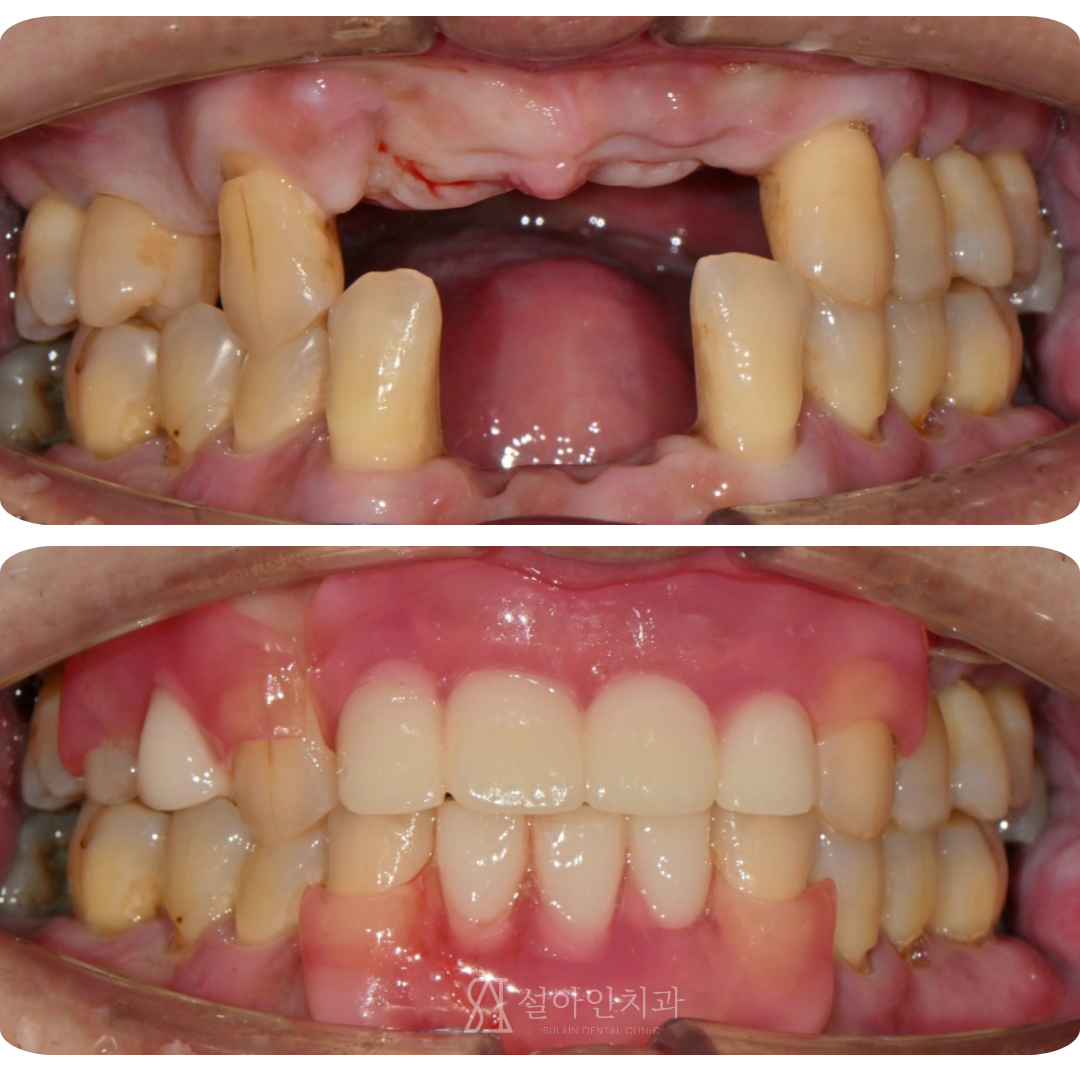

심하게 흔들리는 앞니, 발치 후 치아 없는 기간 없이 바로 해결하는 '3D 디지털 임시틀니'